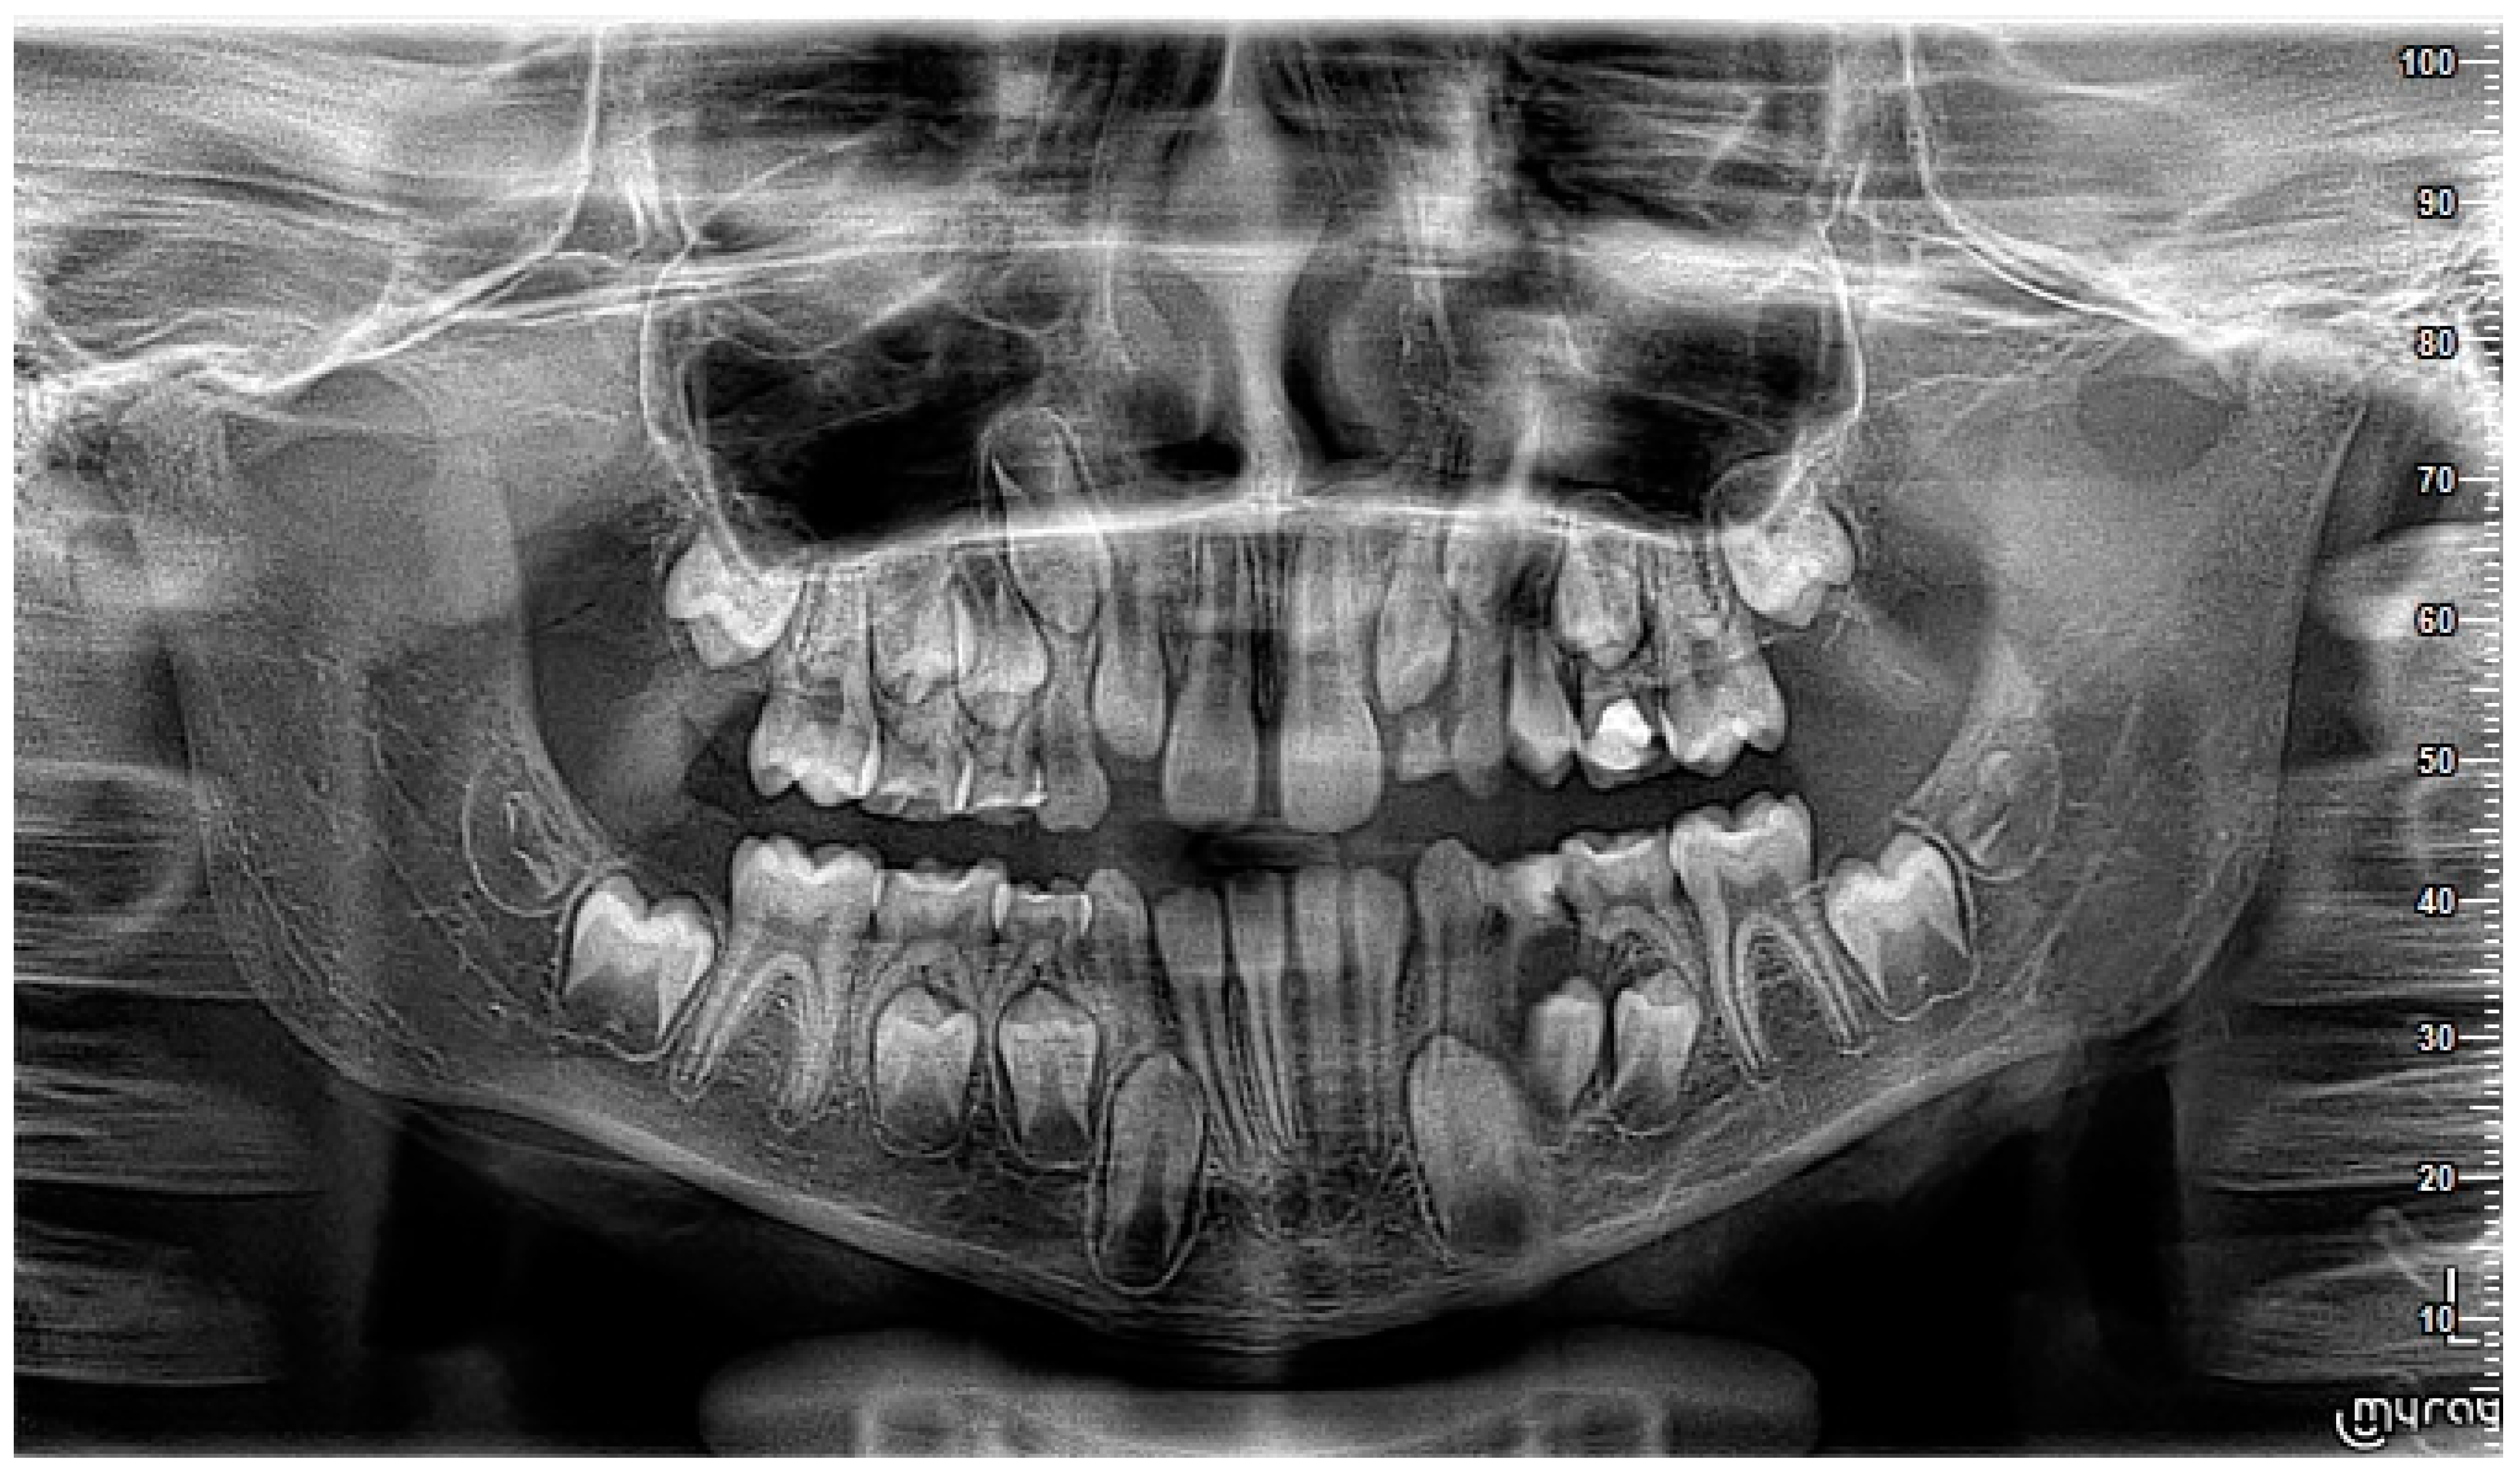

2. Case Report